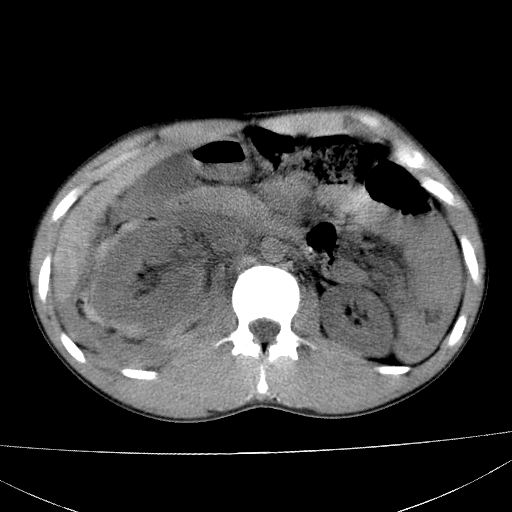

标题: CT15860:男,21岁,腹部外伤2小时伴胸疼。 [打印本页]

标题: CT15860:男,21岁,腹部外伤2小时伴胸疼。

1)肝破裂伴腹腔积液(血)。2)右肾破裂伴右肾包膜下及肾周血肿。3)腹部空腔脏器穿孔可能。4)右侧少量胸腔积液(血)。

肝肾挫裂伤,右肾周及包膜下血肿,腹腔积液,不排除空腔脏器穿孔,建议行增强检查

1肝挫伤伴腹腔积液。2右肾挫裂伤伴右肾包膜及肾后间隙肿血肿。3右肾脏周围的积气,十二指肠显示结构不清,考虑十二指肠降部破裂可能性大。